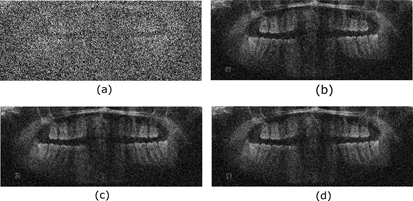

Finally, the radiological images restored using different adaptive filters are presented. Figures 6, 7, 8, and 9 show the noisy and restored images using different 2D adaptive filtering algorithms, respectively. From visual observation, it can be seen that the proposed filter produces a smoother version of the image and, thus, a slightly higher noise reduction compared to the LMS and 2D-NLMS algorithms. Furthermore, the proposed filter improves the visualization of the elements present in the image by more accurately highlighting transitions or edges. This enhancement means that details and structures of interest in the image become more discernible and can be appreciated with greater clarity.

Figure 3 shows the radiological images used for the simulation. These images are available in an open-source database [9]. The access path to the images is as follows: DentalPanoramicXrays.zip → Images → 1.png, 29.png, 58.png, 116.png.